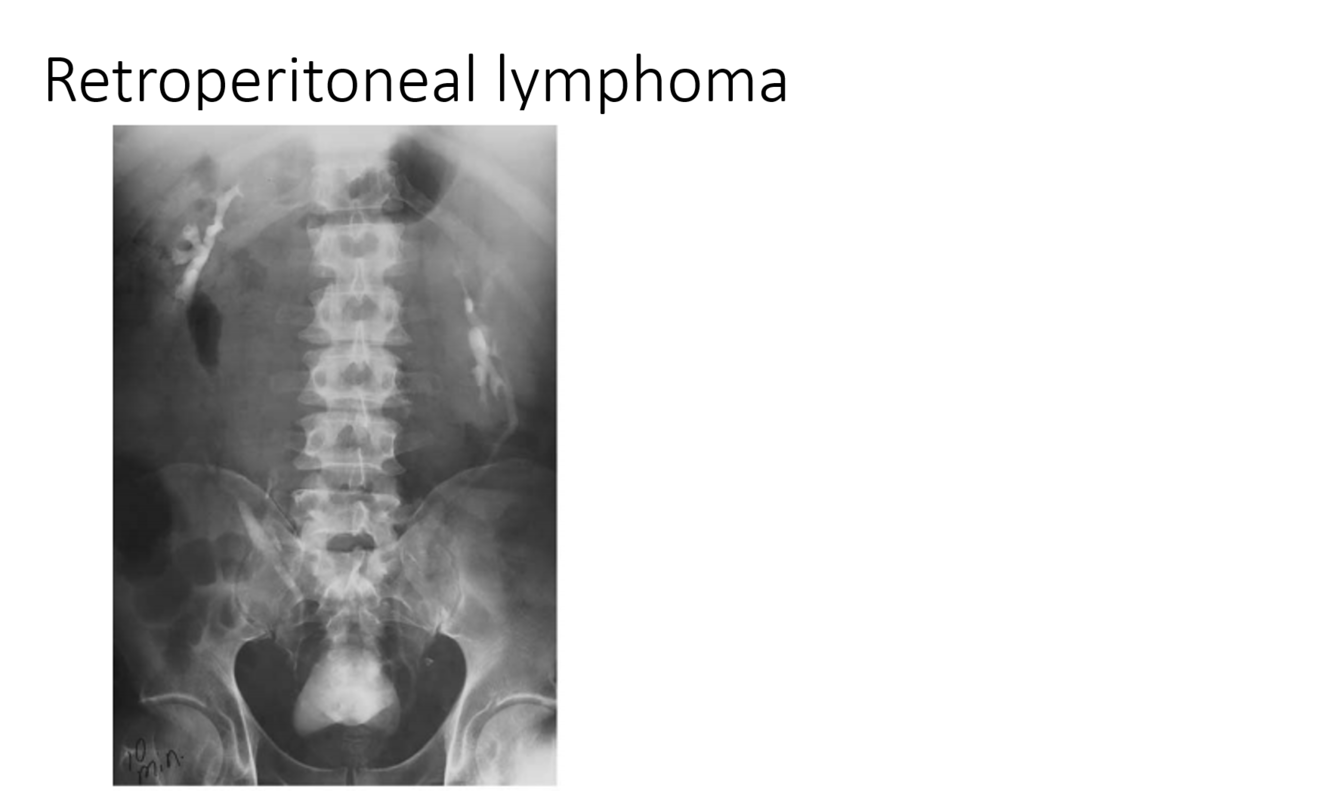

renal sinus cysts

TCC in the renal sinus

multifocal TCC